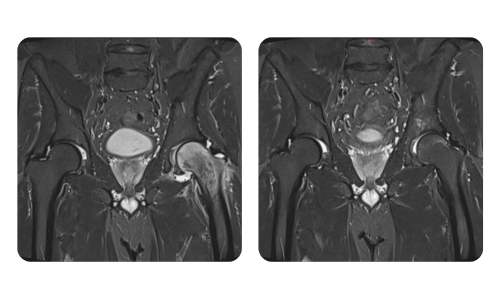

Der Fortschritt unserer Patienten, gemessen vor und nach der hyperbaren Therapie, spiegelt die Effizienz und die positive Wirkung der Behandlung wider. Entdecken Sie dokumentierte Ergebnisse der hyperbaren Therapie in der Klinik Hyperbarium Oradea, basierend auf klinischen Bewertungen und objektiven Daten, die signifikante Verbesserungen bei verschiedenen Erkrankungen belegen.